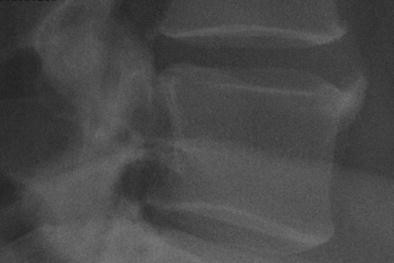

Diffuse idiopathic skeletal hyperostosis (DISH), similar to peripheral calcific entheso/tendinopathy, such as rotator cuff or trochanteric enthesopathies, becomes more prevalent with aging, typically in patients with abnormal metabolism, is asymptomatic in the majority of patients, and can cause persistent and disabling back pain and limitation in others [7]. The anterior longitudinal ligament (ALL), the primary tissue involved in DISH, is a thick band that spans the entire length of the spine, being bound to the periosteum over the vertebral bodies, the margins of the vertebrae, the hyaline cartilage vertebral end plates, and the fibrocartilage disc. As such, the whole ALL can be regarded as an enthesis, and DISH as an axial enthesopathy (Fig. 2). Viewed as such, we posit that if we understood the fundamental difference between silent and clinically significant or pro-inflammatory calcifications in the setting of peripheral calcific enthesopathy and DISH, and/or their activation pathways, this would benefit additional countless patients worldwide.

Calcified vertebral enthesophyte in a patient with DISH